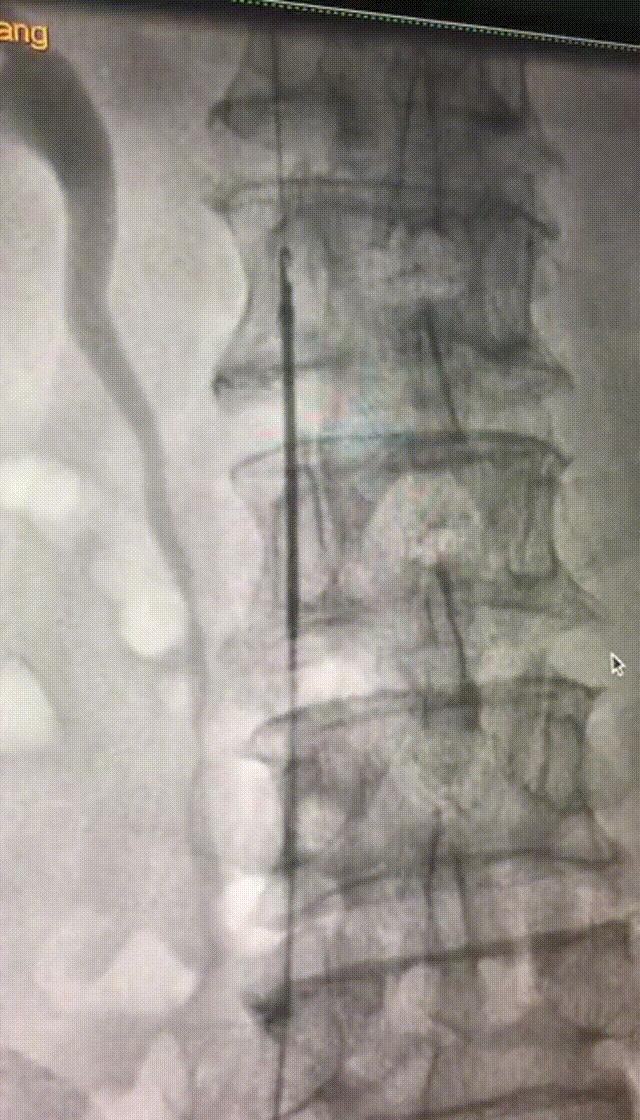

经检查发现该患者左侧股浅静脉、腘静脉均有血栓形成,血栓范围较大,导管室会诊后首先给该患者置入了下腔静脉滤器以防止致死性肺栓塞的发生,而后根据患者的情况制定了个性化的抗凝治疗方案。

成功放置下腔静脉滤器